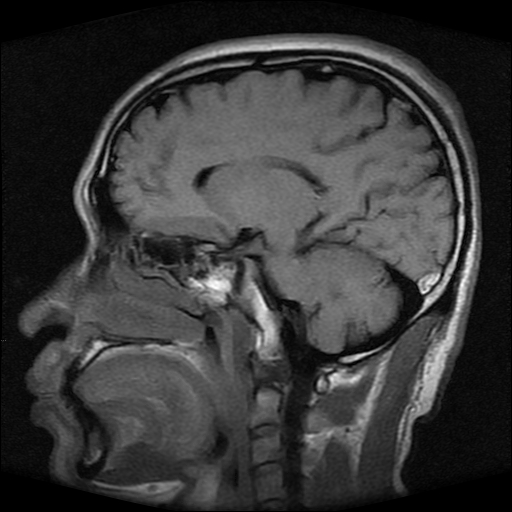

标题: MRI2584:静脉窦血栓?请会诊!

男性,39岁。头晕,视物模糊2月余。血压142/85。矢状窦内高信号有问题吗?

正常脂肪信号影。

正常,若不放心,可以mrv证实

这种病例以前也见过, 但平常的阅片过程比较少注意,而且一些资料上介绍或者图片也比较少,我觉得此病例应该考虑静脉窦血栓。

起码近来我注意的正常人静脉窦内部不是如此信号。

t1wi像可以出现缓慢流速血管呈高信号,应加t2wi及mrv